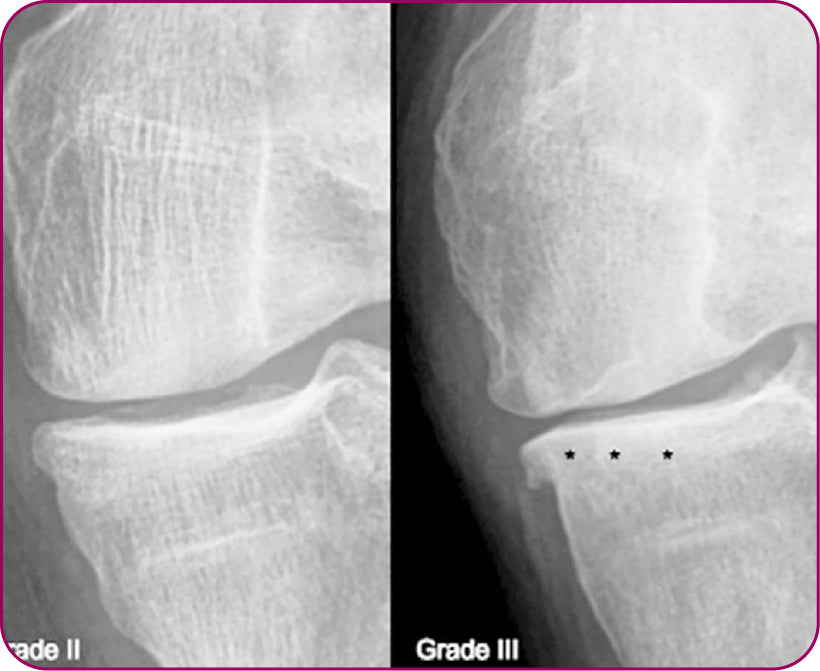

1. Kellgren JH and Lawrence JS. Radiologcal assessment of osteoarthritis.(1957) Ann Rheum Dis 16: 494-502